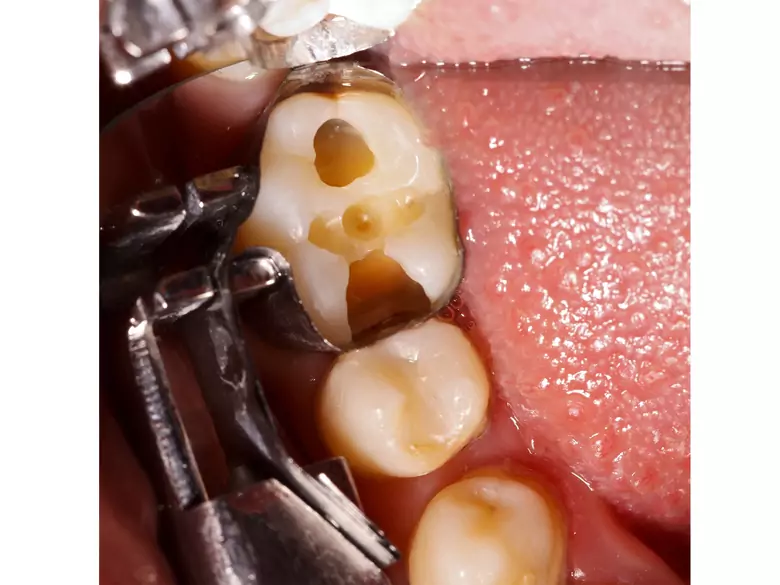

Caries dental - causas, síntomas, diagnóstico, tratamiento

Caries, dientes rotos

Caries